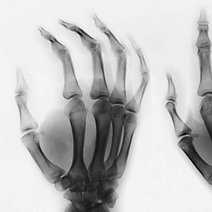

- 强直性柱炎强直性柱炎强直性柱炎(AS)是一种主侵犯柱,并累及关和周围关的慢性性炎性疾病。类湿性柱炎、类湿中心型等,现称AS。由于本病也可侵犯外周关,并在临床、放射线和病理